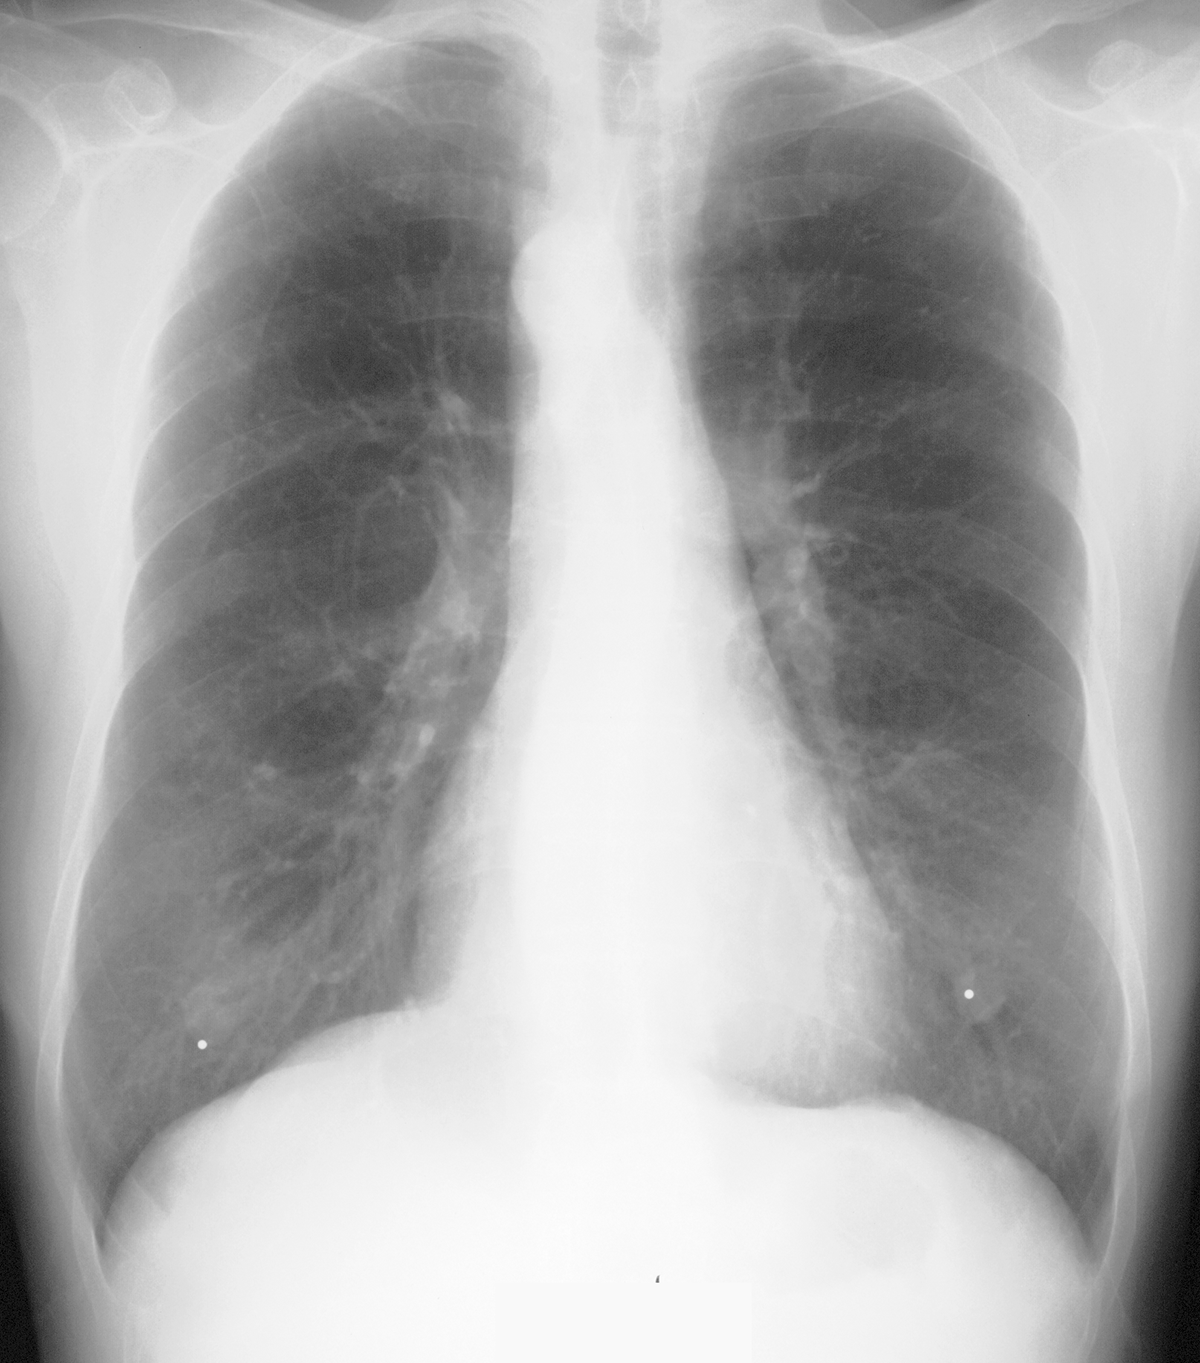

Topic 7

basic case for mediastinal widening

Further Explanation: